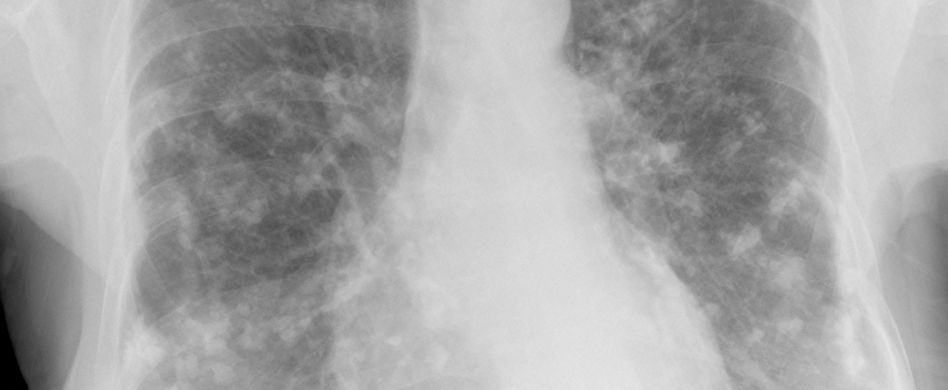

ct bild von lunge

Kalk in der Lunge, pulmonale Verkalkungen genannt, ist ein häufiger Befund im Rahmen einer Computertomografie (CT) der Lunge. Verkalkungen in der Lunge sind oft die Folge ausgeheilter Entzündungen oder einer Schadstoffbelastung, etwa durch Asbest. Häufige Ursachen für Kalkablagerungen in der Lunge.

Kalkablagerungen in der Lunge (Lungenkalzinose) sind oft ein Zufallsbefund einer CT-Untersuchung der Lunge. Die Kalkablagerungen sind eine häufige Folge entzündlicher Prozesse im Lungengewebe. Eine Entzündung der Pleura beispielsweise, also des Brustfells, führt zu einer Umwandlung der dünnen Gefäßwände in verdicktes Gewebe (fibröses Gewebe). Das Gewebe verliert bei Kalkablagerungen in der Lunge an Elastizität und wird steifer. Je stärker die Verdickung des Gewebes ausgeprägt ist, desto stärker ist die Funktion der Lunge eingeschränkt, da sie sich nicht mehr wie gewohnt ausdehnen kann. Manche Kalkablagerungen in der Lunge bleiben vom Betroffenen unbemerkt. Andere führen zu gesundheitlichen Beschwerden wie Atembeschwerden.

Bei der sogenannten Sandsturmlunge (pulmonale Mikrolithiasis) kommt es zu massiven Kalkablagerungen in den Lungenbläschen. Die Lungensteinchen aus Kalziumphosphat werden bis zu 0,3 Millimeter groß. Die Lunge verhärtet und nimmt an Gewicht zu. Etwa 50 Prozent der Fälle treten familiär auf. Oft sind zeigt sich die Erkrankung bereits im Säuglingsalter. Die Sterblichkeit der Betroffenen mit dieser seltenen Erkrankung ist erhöht.